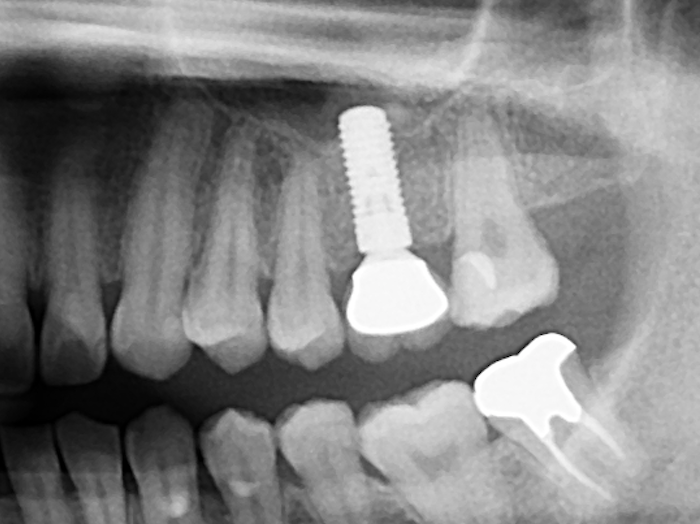

写真は同一部位のレントゲン写真とCT画像です。レントゲン写真は顎骨の形態や走行する神経の位置、歯が生えている方向把握することはできても2次元的な位置関係でしか把握できません。つまり歯や神経の位置がわかっていても実際にどのくらいの位置関係にあるのかを正確に判断することはレントゲン写真では不可能なわけです。しかし、歯科用CT画像では顎骨の形態や走行する神経の位置、歯の生えている方向、さらには骨密度の状態を3次元的に画像化する事が可能なため、より正確な診断する事ができます。